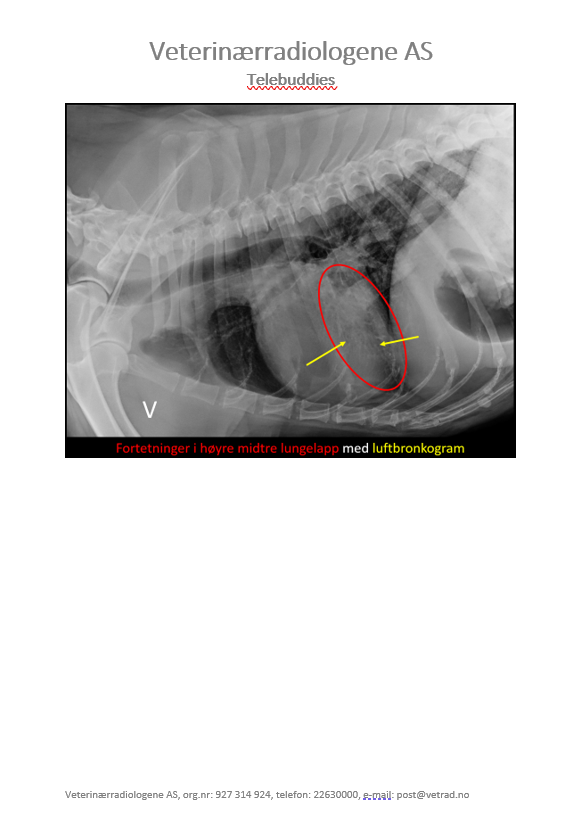

Denne gangen har vi lyst til å dele et kasus som vi syns er ganske interessant. Studien ble sendt inn til oss fra Dyrlegene i Skolestua, og sammen kom vi frem til en diagnose som kan forklare hundens problemer. Signalement: Pyreneerhund, tispe, 9år Anamnese: Eier syns hunden har blitt i dårligere form over tid, den bruker lang tid på å spise, tiltagende hosting. Eier har sau, så hunden jobber som vokterhund. Etter anstrengelse bruker hunden lang tid på restitusjon, peser lenge.